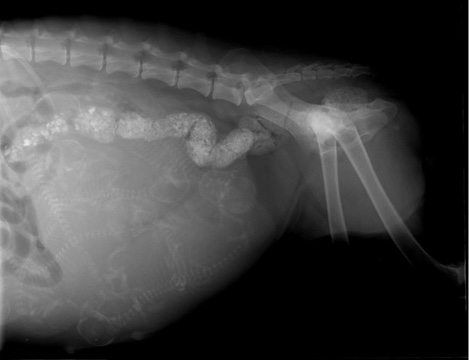

Figure 1

Abdominal (Latro-lateral) roentogram of PT affected bitch clearly showing fetus numbers.